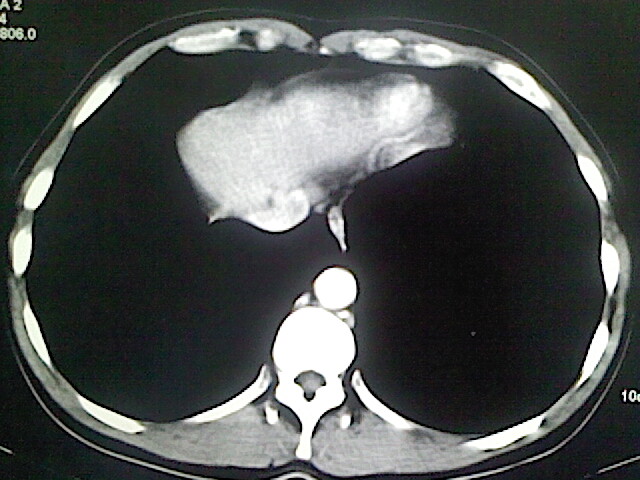

以下是引用卜一在2009-3-14 9:49:00的发言:[br]胆囊萎缩,胆囊壁不规则增厚,内部结构模糊,增强明显强化。另:肝左叶外侧段肝囊肿。支持:慢性胆囊炎!高度可疑:胆囊癌!

以下是引用余辉在2009-3-14 8:48:00的发言:[br]1)慢性胆囊炎。2)肝左叶外侧段肝囊肿。3)脂肪肝。[br]支持,胆囊萎缩,密度增高,不知b超具体有何提示,钙胆汁?结石?

以下是引用jiangjing在2009-3-14 10:18:00的发言:[br]1)慢性胆囊炎。2)肝左叶外侧段肝囊肿。3)脂肪肝。4.】建议行肝功能检查